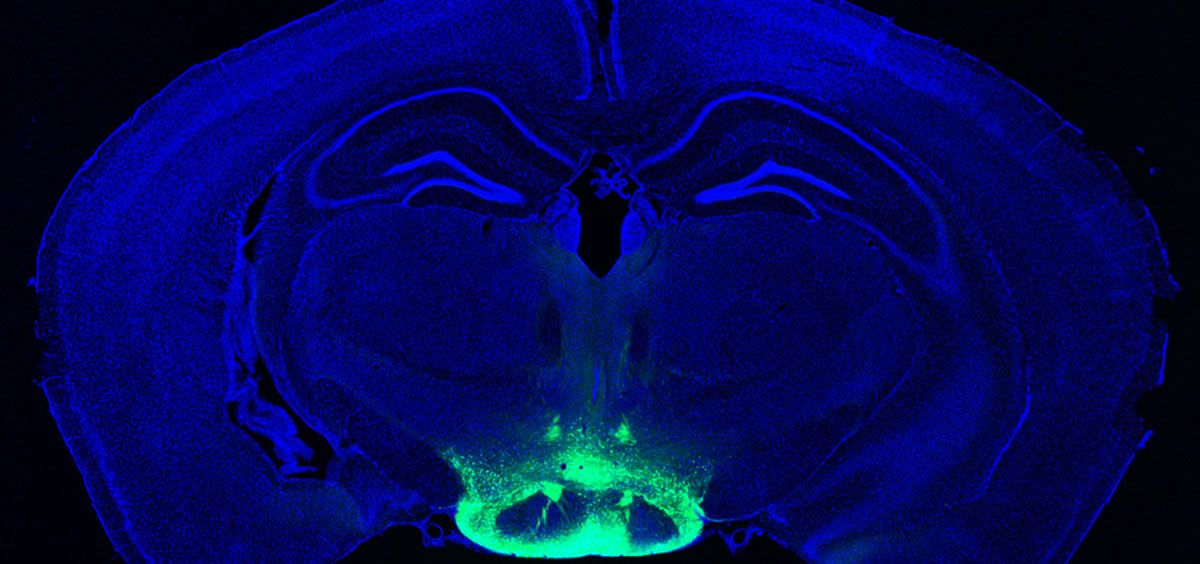

Dentro de la compleja estructura cerebral, existe un grupo de neuronas conocidas como el cuerpo mamilar. Un conjunto de neuronas de pequeño tamaño en el hipotálamo que parece que presenta mayor acumulación de la beta amiloide asociada a la neurodegeneración. Este órgano no es desconocido, se ha asociado muchas veces con el síndrome de Wernicke-Korsakoff, un trastorno cerebral grave producido por la deficiencia de tiamina y que se caracteriza por confusión mental, desorientación o dificultad para crear nuevos recuerdos

En los últimos años los cuerpos mamilares se han relacionado también con esquizofrenia y con alzhéimer. En 2019, un primer estudio del MIT en ratones evidenció que la acumulación de placas de proteína amiloide empieza en la región profunda del cuerpo mamilar antes de abrirse paso a lo largo de circuitos cerebrales específicos y llegar al hipocampo. “Es realmente fundamental comprender qué circuitos y regiones muestran disfunción neuronal al principio de la enfermedad. Esto, a su vez, facilitará el desarrollo de terapias efectivas”, explicaba entonces el coautor del estudio, Li- Huei Tsai, Profesor Picower de Neurociencia y director del Instituto Picower.

Cuatro años después, parte de ese primer equipo investigador ha publicado en ‘Science Translational Medicine’ nuevos resultados en los que observaron que parte del cuerpo mamilar reacciona de forma “desproporcionada” y acumula más placa amiloide, y hallaron una forma de tratarlo. Para ello los investigadores secuenciaron el ARN de una célula e identificaron dos poblaciones de neuronas: el cuerpo mamilar medial y el cuerpo mamilar lateral. Los investigadores descubrieron que las neuronas laterales eran más hiperactivas durante el envejecimiento y más susceptibles a la neurodegeneración.